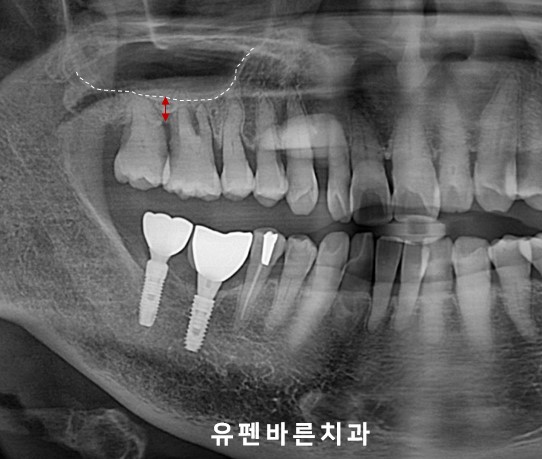

(첫번째 케이스)

Teeth No. #2,3 Sinus Augmentation

왼쪽 위사진을 보시면

인공뿌리(임플란트)를 식립하기에는

빨간 화살표 처럼

뼈의 높이가 많이 짧아 보입니다.

이런 경우

그냥

임플란트만 식립하게 되면

임플란트 길이의 80%가 단단한 뼈안에

고정되지 않고

상악동의 허공에

뜨게 됩니다.

헉!!!

그렇게 되면

임플란트가 뼈에 제대로 고정되지 못하고

흔들리며

임플란트 실패의 결과로

이어지게 됩니다.

따라서!

오른쪽 위사진의

빨간색 화살표 만큼의

상악동 거상(들어올림)과

인공뼈이식을 통해

충분한 뼈높이를 만든 후

임플란트를 식립해야

안전하고 이상적인 임플란트 수술을

마칠 수 있습니다 :)

마무리 된

상악동 거상과 뼈이식이

반구형 모양(Dome-Shape)으로

아주 예쁘게 잘 올라간 모양을

보실수 있습니다.